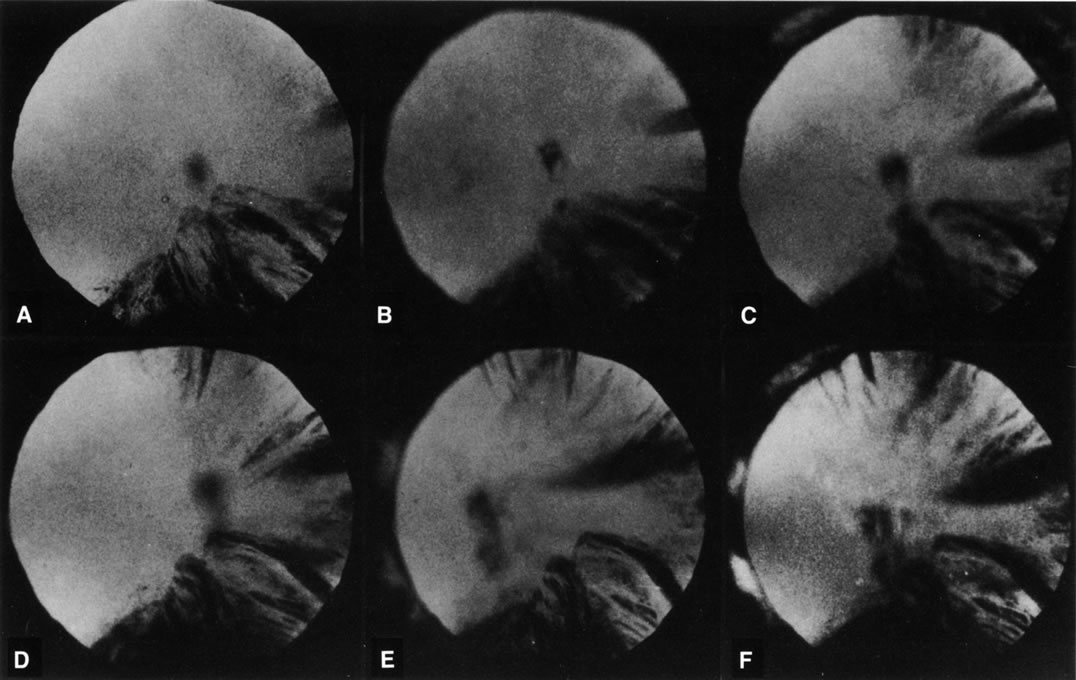

Fig. 8. Follow-up retroillumination photographs of an eye with a cortical cataract, obtained at various intervals. A. First visit (1-21-87); B. 1 year later (1-27-88); C. 22 months later (11-14-88); D. 28 months later (12-4-89); E. 35 months later; F. 41 months later (6-18-90). With such photographs one may be able to plot the progression rate of a cortical cataract, and aid in performing longitudinal studies. Note the central opacity, which is out of focus and represents a small posterior subcapsular cataract.

Retroillumination uses the light reflected from the fundus to highlight opacities. This is very useful in examining cortical and posterior subcapsular cataracts (Figs. 1, 3, 7, and 8). However, some cortical water clefts and early posterior subcapsular opacities may not be easily seen with retroillumination if they are not dense enough to cast shadows or only refract the retroilluminate light; these can be best seen with the broad beam. Using retroillumination on nuclear cataracts does not give much information because these usually do not cast shadows. However, as seen in Figure 2B, a change in the refractive index can be seen toward the center. Usually, the outline of the nuclear cataract can be seen as a result of a “magnifying lens” artifact. This is also easily observed during direct and indirect ophthalmoscopy. Several retroillumination cameras (modified slit lamps with the slit beam fixed for retroillumination and depolarizers built in to remove corneal reflex from the image) have been developed and are being used for documenting cortical and posterior subcapsular cataracts.49, 50

Retroillumination cameras49,50 obtain images of cortical and posterior subcapsular cataracts as shown in Figures 1B, 7, and 8. These are useful for both cross-sectional and longitudinal studies. Various manual or automated methods have been developed or are being developed for the analysis of these images to determine the size of opacities. Usually, an artificial mask with a chosen diameter is used to standardize the area of interest in the image, and either a percent area or area in square millimeters is determined. Because of the variability of the background light (the images are shadows of the cataracts using light that is backlighted from the retina or optic nerve), densitometry is unreliable. Among the methods used include computer planimetry, counting boxes, manual and automated edge detection, and automated area analysis. This method is also being used to study IOL decentration and posterior capsular opacification after cataract surgery. Examples of this type of device are the Nidek EAS 1000 retroillumination unit (Nidek, Pasadena, CA), Oxford retroillumination camera (Marcher Ltd., Hereford, UK), and Topcon CTR (Topcon Medical Systems, Paramus, NJ).